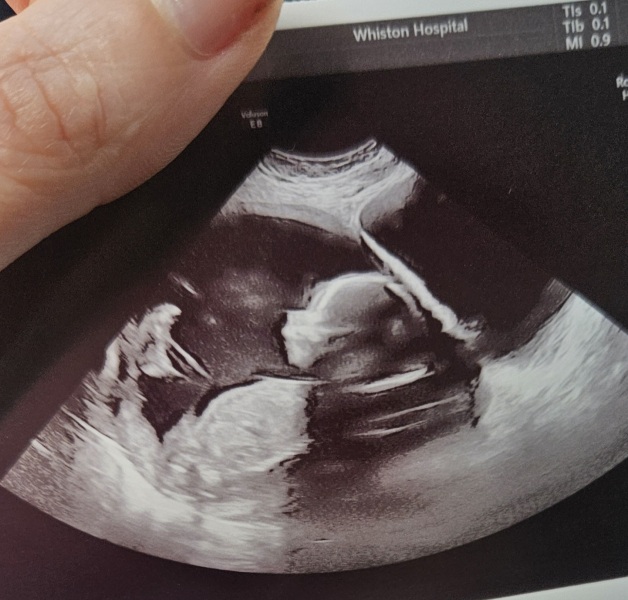

All went well thankfully 🥰 baby is well and wouldn't stop moving around...almost too much 🙈 measuring on the 49th percentile atm so assuming that's average? Xx

@SnookyPook nope OH told them straight away so she kept turning the screen away 🤣 it's giving me slight girly vibes now but I guess I'll just have to wait and see 🤣 pic isn't super clear as it was like bouncing all over the show....it was bum down feet on my bladder too 😫 which weirdly I already knew as the kicks have been sooo low down and I need to wee alot 🤣

Lovely news @Westy22 , so glad that everything went well. Looks like you have a very active little person in there!